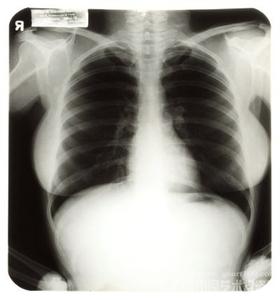

X光片是患者做手术的重要依据,在中山,一位患者做了两次手术后发现医院提供的X光片是别人的。这张X光片引发了此后的四次诉讼。病人状告医院赔偿后续治疗费、终身后续治疗费等6亿多元。

12月22日,因阿芬感到严重不适,医生再为其X光片检查,在说明相关情况后医生建议阿芬镜下调整“J”管,以减轻对肾盂的刺激,但在阿芬坚持下,同日,医生为其拔除了留置的双“J”管。29日,阿芬康复出院,复印病历时发现22日检查的X光片不是本人的X光片。

法院在民事诉讼中,依法委托中山大学法医鉴定中心对涉案全部医疗行为进行鉴定,但因2010年12月22日检查X光片缺失,鉴定机构终止了鉴定。最后,法院依举证倒置的规定,推定医院医疗行为存在过错,承担全部责任,判决医院向阿芬支付医疗费、住院伙食补助、护理费、误工费、营养费元、交通费、精神抚慰金合计3万余元并驳回阿芬其他诉讼请求。阿芬不服,提起上诉,中山中院二审民事判决驳回阿芬上诉,维持原判。